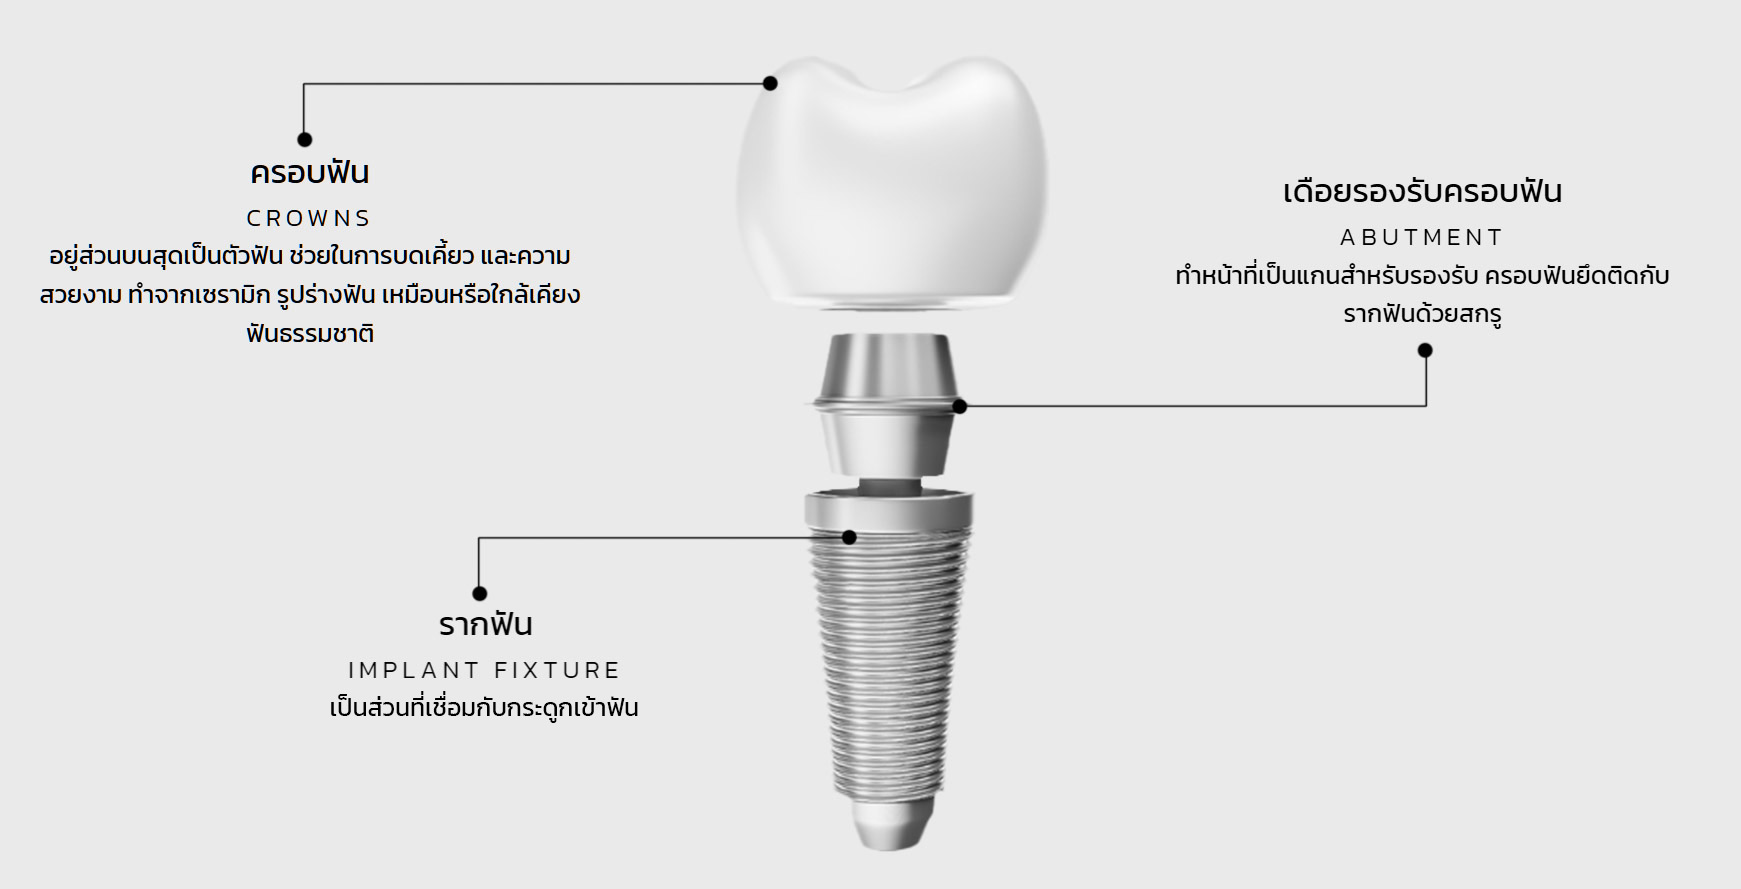

ครอบฟัน

CROWNS

(ส่วนบนสุด) เป็นตัวฟัน ช่วยในการบดเคี้ยว และความสวยงาม ทำจากเซรามิก รูปร่างฟัน เหมือนหรือใกล้เคียงฟันธรรมชาติ

เดือยรองรับครอบฟัน

ABUTMENT

(ส่วนกลาง) ทําหน้าที่เป็นแกนสําหรับรองรับ ครอบฟันยึดติดกับรากฟันด้วยสกรู

รากฟัน

IMPLANT FIXTURE

(ส่วนล่างสุด) เป็นส่วนที่เชื่อมกับกระดูกเข้าฟัน